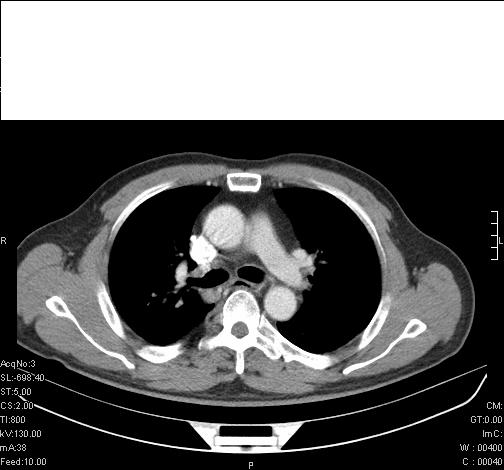

标题: CT6685:右肺阻塞性炎症,增强CT。

前几天,发了患者的平扫片,患者抗炎一周后增强扫描。右中叶病灶吸收明显,但下叶病灶未见明显吸收。右肺门可见结节影,看来凶多吉少

右肺下叶支气管壁明显增厚,考虑癌症并阻塞性炎症、肺门淋巴结肿大

考虑右肺癌并阻塞性炎症、肺门淋巴结肿大

还是考虑右肺中央型肺癌可能性大

右肺下叶支气管壁不规则增厚,右肺下叶有斑片状影分布。考虑右肺中央型肺癌伴右肺下叶阻塞性改变。建议支纤镜检查。平扫比增强较好显示了病变情况。

考虑右肺中央型肺癌可能性大

右主支气管狭窄,管壁增厚。考虑右中心性肺ca伴阻塞性肺炎。